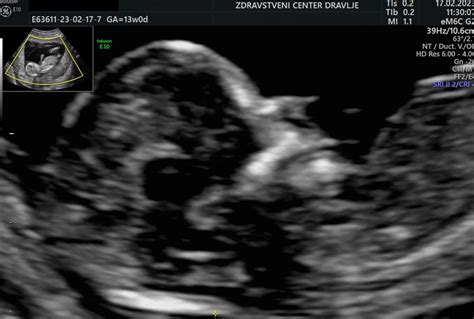

Merjenje nuhalne svetline je neinvazivni prenatalni test, ki ocenjuje debelino kože na zadnji strani otrokovega vratu. Ta test lahko ponudi zgodnjo indikacijo kromosomskih nepravilnosti, kot je Downov sindrom, ter drugih strukturnih težav. S tem staršem zagotavlja informacije, ki jim lahko pomagajo pri nadaljnjem odločanju o poteku nosečnosti.

Ultrazvočno merjenje nuhalne svetline je najučinkovitejše med 11. in 14. tednom nosečnosti. Idealen čas za pregled je med 11. tednom (ko je dolžina ploda približno 45 mm) in 13. tednom nosečnosti (ko je dolžina ploda približno 84 mm). V tem obdobju je nuhalna svetlina najbolj zanesljiv pokazatelj. Čeprav je mogoče pregled opraviti tudi kasneje, se lahko natančnost meritve zmanjša.

Za natančno merjenje nuhalne svetline je ključno, da ima nosečnica izpraznjen sečni mehur, kar omogoča boljši prikaz medeničnega dela in s tem boljše ultrazvočne meritve. Pomembno je tudi, da je plod v ugodni legi za pregled. Preiskava običajno traja približno 15 minut in se izvaja preko trebušne stene.

- Merjenje velikosti ploda: Določimo dolžino ploda od vrha glavice do trtice (CRL - Crown-Rump Length), kar pomaga pri določanju gestacijske starosti in predvidenega datuma poroda.

Natančnost testa in kaj pomeni povečana nuhalna svetlina